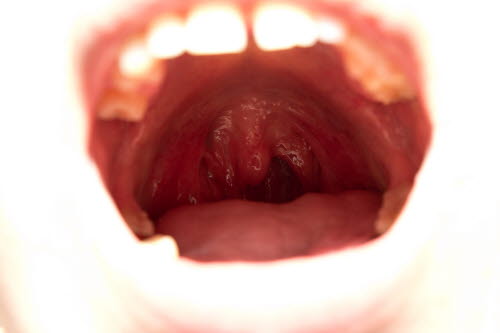

Kreft blir ofte beskrevet som ukontrollert cellevekst. Celler som har mistet evnen til å kontrollere sin egen vekst. Dette fører til oppsamling av denne celletypen på ett eller flere steder, og det dannes en svulst eller flere svulster. Slike svulster kan oppstå i bakre del av munnhulen og svelget, i orofarynks. Den vanligste lokalisasjonen for slike svulster er rundt mandlene.

På ethvert tidspunkt er det cirka 5000 personer med kreft i munnhulen eller svelget i Norge, og det oppstår vel 600 nye tilfeller per år.